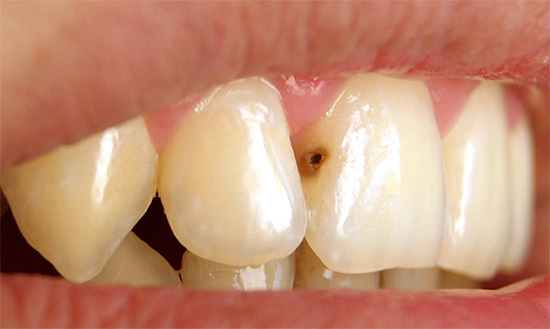

Foto di carie profonde sul dente anteriore: